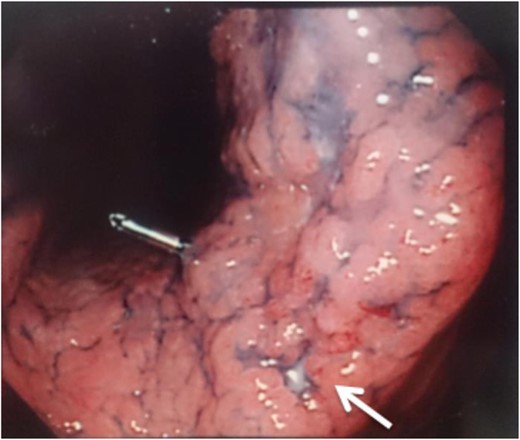

A 56-year-old man presented to our institution with esophageal and gastric cancer. Esophagogastroduodenoscopy (EGD) demonstrated a type 2 tumor occupying one-third of the circumference of the esophagus and measuring 28–33 cm from the incisors (Fig. 1). Endoscopy revealed that the tumor invaded the muscularis propria and biopsy revealed SCC. Moreover, a type 0-IIb tumor was located at the lesser curvature of the angle of the stomach. Endoscopy revealed invasion of the mucosa and biopsy revealed adenocarcinoma (Fig. 2). Computed tomography (CT) showed no enlarged lymph nodes in the mediastinum or distant metastasis in the liver or lung. Therefore, the patient underwent thoracoscopic esophagectomy (video-assisted thoracic surgery for esophagus), 2-field lymph node dissection, partial gastrectomy and gastric tube reconstruction via a retrosternal route for the advanced esophageal and early gastric cancers. Histopathologic analysis revealed Stage II (type 2, T3, ly2, v0, N0, PM0, DM0) esophageal and Stage I (type 0-IIb, T1, ly0, v0, N0) gastric cancer, with positive horizontal margins of dissection of the gastric cancer. Therefore, as additional treatment, we performed argon-plasma coagulation around the dissected gastric mucosa postoperatively.

A type 0-IIb tumor located at the lesser curvature of the angle of the stomach on esophagogastroduodenoscopy.